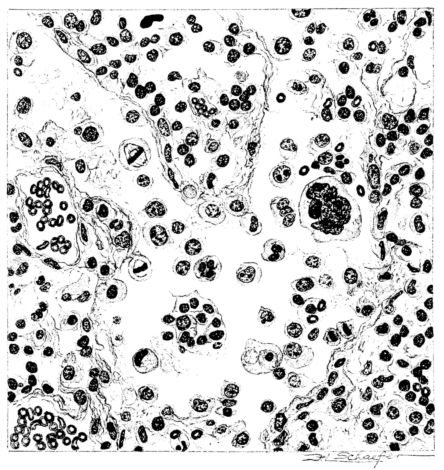

FIG. XXIII. AUTOPSY NO. 175. NOTE THE ABSENCE OF ALVEOLAR EPITHELIUM, THE ENGORGEMENT OF THE VESSELS OF THE ALVEOLAR WALLS, AND THE SEROUS EXUDATE.

No matter what the portion of the lung from which the sections are derived, the fundamental changes found are the same. The subpleural sheets are spread wide apart, now by empty spaces, now by coagulated fluid. The process extends from the surface through the interlobular septa (Fig. XX), and is accentuated where the connective tissue is more prominent around vessels and bronchi. The nature of the infiltrate in the subpleural and interstitial tissues becomes more evident in the alveoli, which likewise are filled. The material varies somewhat in appearance, probably dependent upon its proteid content. Not infrequently the alveoli contain a homogeneous, pink-staining mass, which resembles the colloid of the thyroid gland. Again, it may be simply a coarse granular precipitate (Fig. XXIII), and in still other instances, small sticks and strands form the bulk of the alveolar content (47, 92, 140, 156). This subpleural, interstitial, perivascular, peribronchial, and alveolar edema, which is a term applicable to this collection of fluid, is very prominent, and although its intensity varies in different portions of the lung; and although it may be replaced in some areas by other types of exudate, unquestionably, this is the dominating expression of the inflammatory process in the early stage of the disease.

As might be expected from the gross appearance, the alveoli vary in size. At times slightly collapsed and at other times overdistended, their lumina are still the seat of the inflammatory exudate, although the mechanical change may allow of some variation in the appearance of their walls. As a rule, however, the alveolar wall is prominent and owes its conspicuousness to the tortuous, engorged vessels within. These vessels contain red blood cells almost exclusively, and on account of the partial, occasionally complete, loss of the lining epithelium, the alveolar wall appears as a huge, dilated arteriole (101) separating the lakes of coagulated material in the spaces (Fig. XXIII). There are areas, as indicated above, where the alveolar content may be more definitely arranged in the form of beaded or homogeneous strands of different caliber; the smallest resemble delicate threads. They tend to converge toward the alveolar wall like wheat in a sheaf, and often pass through this wall by way of the so-called pores of Cohn; as soon as the body of the neighboring alveolus is reached, they again present a fan-like expansion into innumerable, fine strands (Fig. XXII). Where the exudate is more fibrinous, the alveolar wall is less likely to be distended, its vessels are not so prominent, and their content of red blood cells is definitely decreased. Still this is not the most extreme type of alveolar exudate met with at this stage. Perhaps, the most striking, although not the most frequent, exudate has a superficial resemblance to a huge, red blood clot, and it may be difficult to make out the alveolar walls separating the masses of well preserved red blood cells that fill the alveolar spaces. These areas are indistinguishable from infarcts and may be associated with thrombotic arteritis in near-by pulmonary vessels (47) (Figs. XXIV and XXV). Among the red blood cells an occasional strand of fibrin, a desquamated alveolar epithelial cell, and rarely a polymorphonuclear leucocyte may be encountered. The alveolar wall itself varies in the definition of its outline. When its vessels are greatly distended, when its alveolar epithelium is gone, and when its content consists largely of red blood cells, it is difficult to distinguish from the exudate which it encloses. However, when it is more compressed or when its epithelial lining cells are still more or less intact, it may be seen as a blue-staining strand under the low power of the microscope, for the well preserved nuclei lend it prominence.